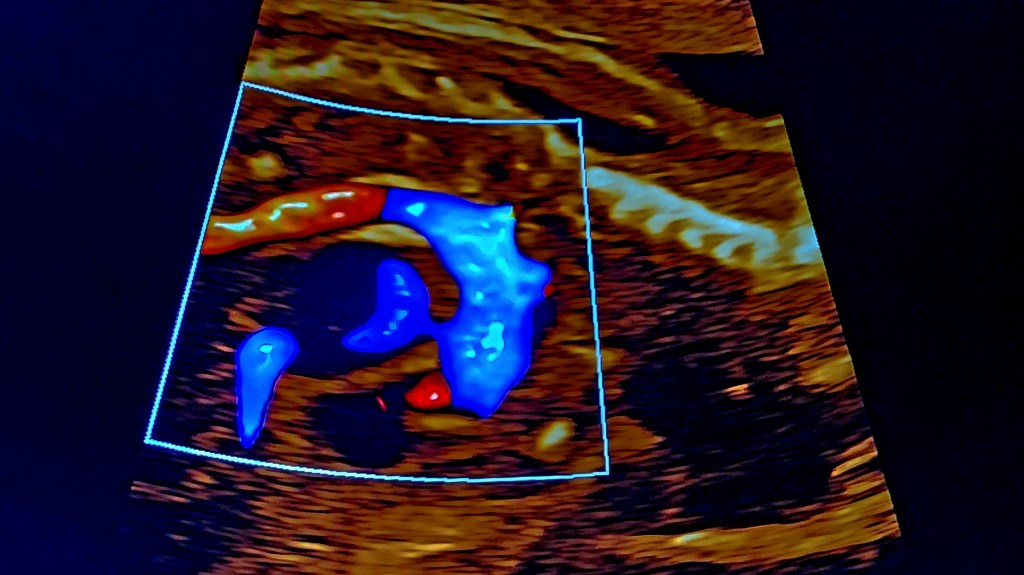

Fetal Ductal Arteriosus Restriction: A Practical, Objective Approach

The fetal heart works quietly in balance, guided by pathways meant for a temporary life before birth. The ductus arteriosus is one such bridge—essential, adaptable, and vulnerable. When its balance shifts too early, subtle changes ripple through the right heart, long before symptoms are visible.